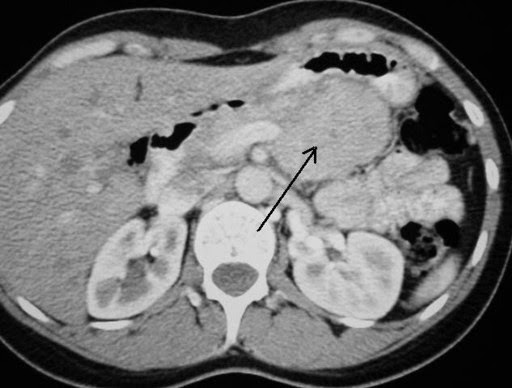

Δεν υπάρχει έλεγχος ρουτίνας για τους NET, ωστόσο κοινά εργαλεία που χρησιμοποιούνται για τη διάγνωσή τους είναι οι σαρώσεις αξονικής τομογραφίας (CT), η απεικόνιση μαγνητικού συντονισμού (MRI), το υπερηχογράφημα και το σπινθηρογράφημα υποδοχέων σωματοστατίνης.